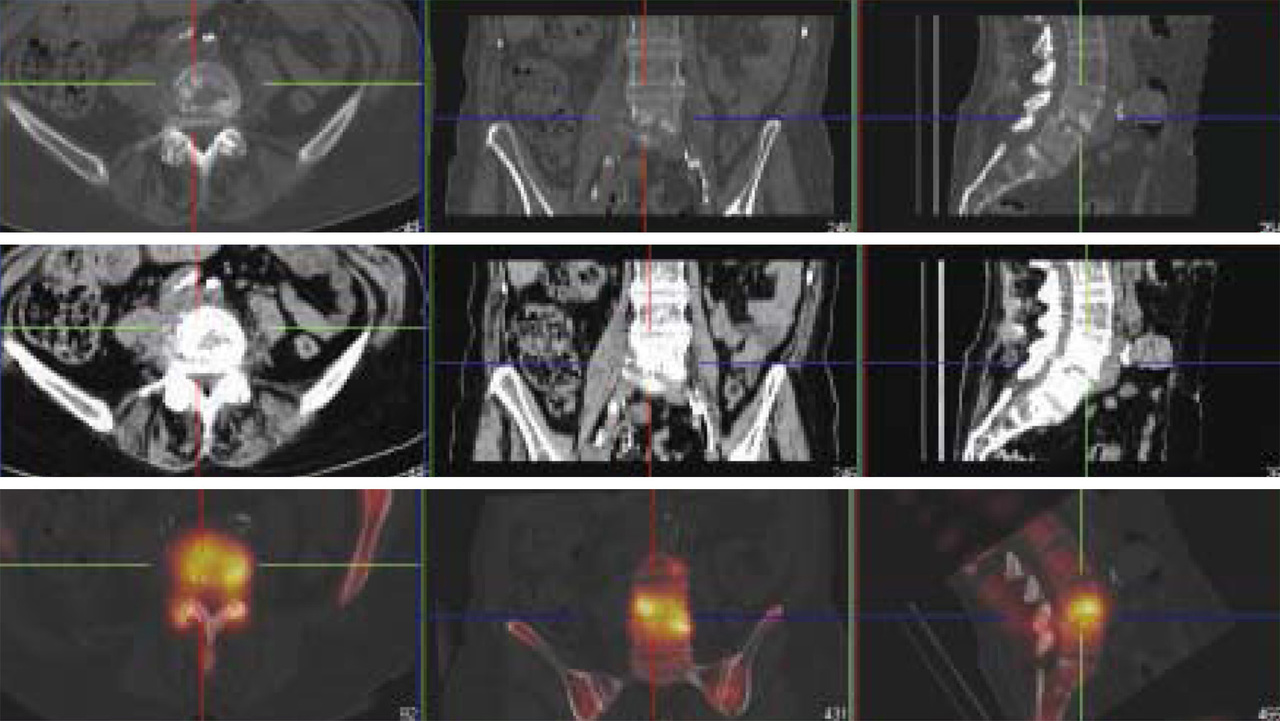

Spondylodiscite lombaire.Tomoscintigraphie couplée à une tomodensitométrie (TEMP-TDM), courtoisie du Centre havrais de médecine nucléaire.